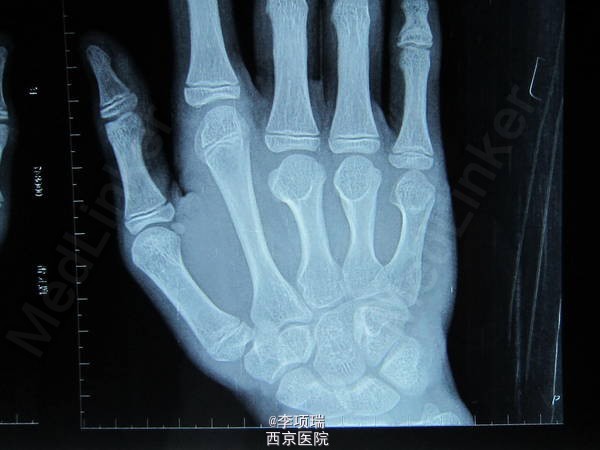

你见过这样的畸形吗?

患者15岁,男性。这个患者大家看怎样手术?何时手术?